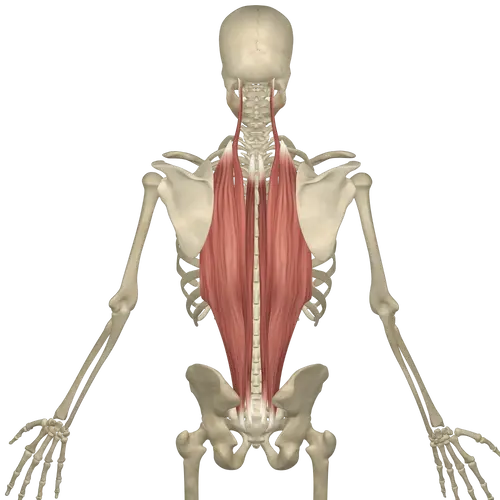

Erector spinal release

You can also release your erector spinal muscles (figure 2). By rotating to your back and placing the ball on a side of your spine and placing and leaning your weight in to it in a straight up and down or diagonal fashion to getter hit the trigger point. To add more weight bring heals comfortably close to your butt and then cross the leg on the treatment side so that u would be sitting like a masculine man not a femboy. (Ankle on knee)

Erector spinal release

You can also release your erector spinal muscles (figure 2). By rotating to your back and placing the ball on a side of your spine and placing and leaning your weight in to it in a straight up and down or diagonal fashion to getter hit the trigger point. To add more weight bring heals comfortably close to your butt and then cross the leg on the treatment side so that u would be sitting like a masculine man not a femboy. (Ankle on knee)